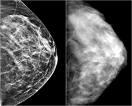

Women’s imaging, more specifically breast imaging, faces tremendous cost and technology challenges for the retention and access over the long-term to meet regulatory compliance and clinical requirements. While digital mammography exams can range from 60-120 MBs per study, emerging techniques for tomosynthesis can more than double these data sizes. Moreover, breast MR can exceed 800 MBs per exam. Combining these diagnostic tests with interventional guided imaging can amass large data sets associated with any particular imaging exam. Subsequent access to portions of this data is required for comparison upon annual recall of patients.

With over 10,000 locations providing imaging for woman’s’ health, the capabilities for the unique management of this imaging data varies greatly. The workflow and presentation of data sets are often best served by mammography vendors’ specific workstations outside of the classic PACS. Solutions that offer DICOM management of the data as a service eliminates the costly overhead of data management from these clinical environments.